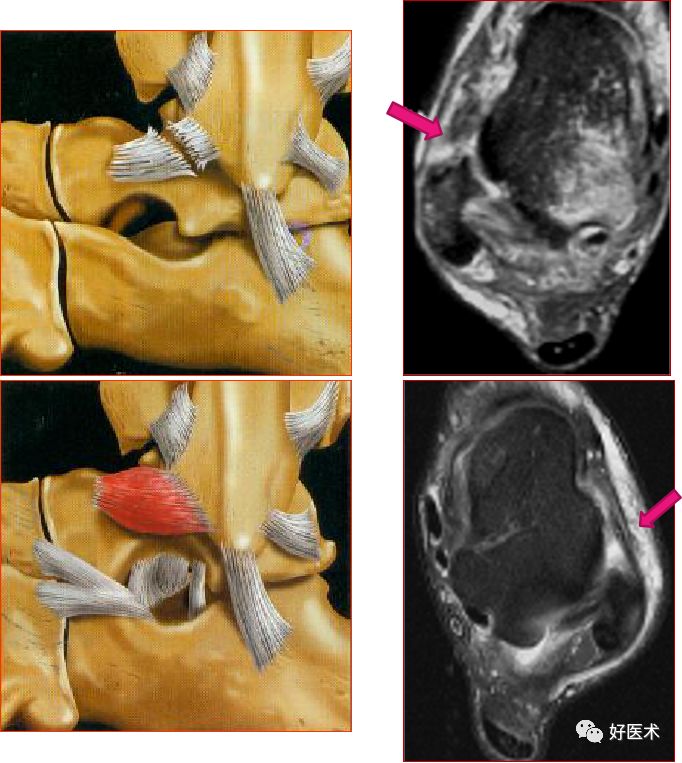

距腓后韧带部分撕裂

跟腓韧带

跟腓韧带急性完全撕裂